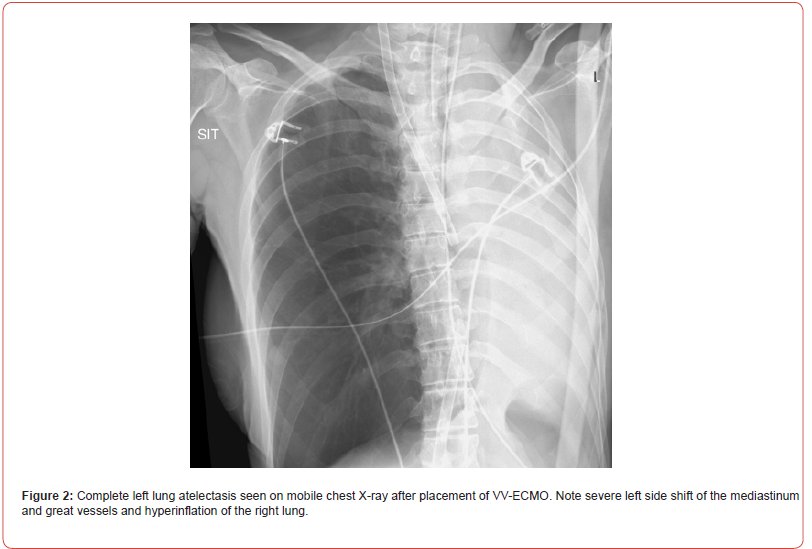

Shortly after, the situation escalated rapidly; the patient experienced a sudden desaturation to 70% and was emergently intubated. Mobile chest x-ray revealed complete atelectasis of the left lung (figure 1). Immediate bronchoscopy showed large amount of blood and blood clots in the left main bronchus and despite ongoing suctioning, the left lung did not re-inflate and the patient remained severely hypoxic. Few hours later a venous-venous extra-corporal membrane oxygenation (VV-ECMO) was emergently placed due to refractory hypoxemia (figure 2). In the following days, the patient’s lungs did not re-inflate despite multiple bronchoscopies performed due to ongoing bleeding that filled the airways with blood clots up to the upper trachea (figure 3). Tracheostomy was placed but blood clots filled also the tracheostomy tube that needed to be capped to prevent ongoing blood loss. The patient was treated with full VV-ECMO support, disconnected from the ventilator due to zero tidal volume secondary to the blocked trachea, and in the following weeks developed septic shock and acute renal failure requiring hemodialysis. In attempt to stop the ongoing bronchial bleeding the patient was transferred almost daily to the radiation oncology unit to receive radiation while on VV-ECMO (20 Gy in 10 fractions over 2 weeks) to the proximal tracheobronchial tree [4]. During and after completion of the radiation, multiple bronchoscopies aimed at controlling bronchial bleeding and clearing airway obstructions were conducted, unfortunately unsuccessfully.